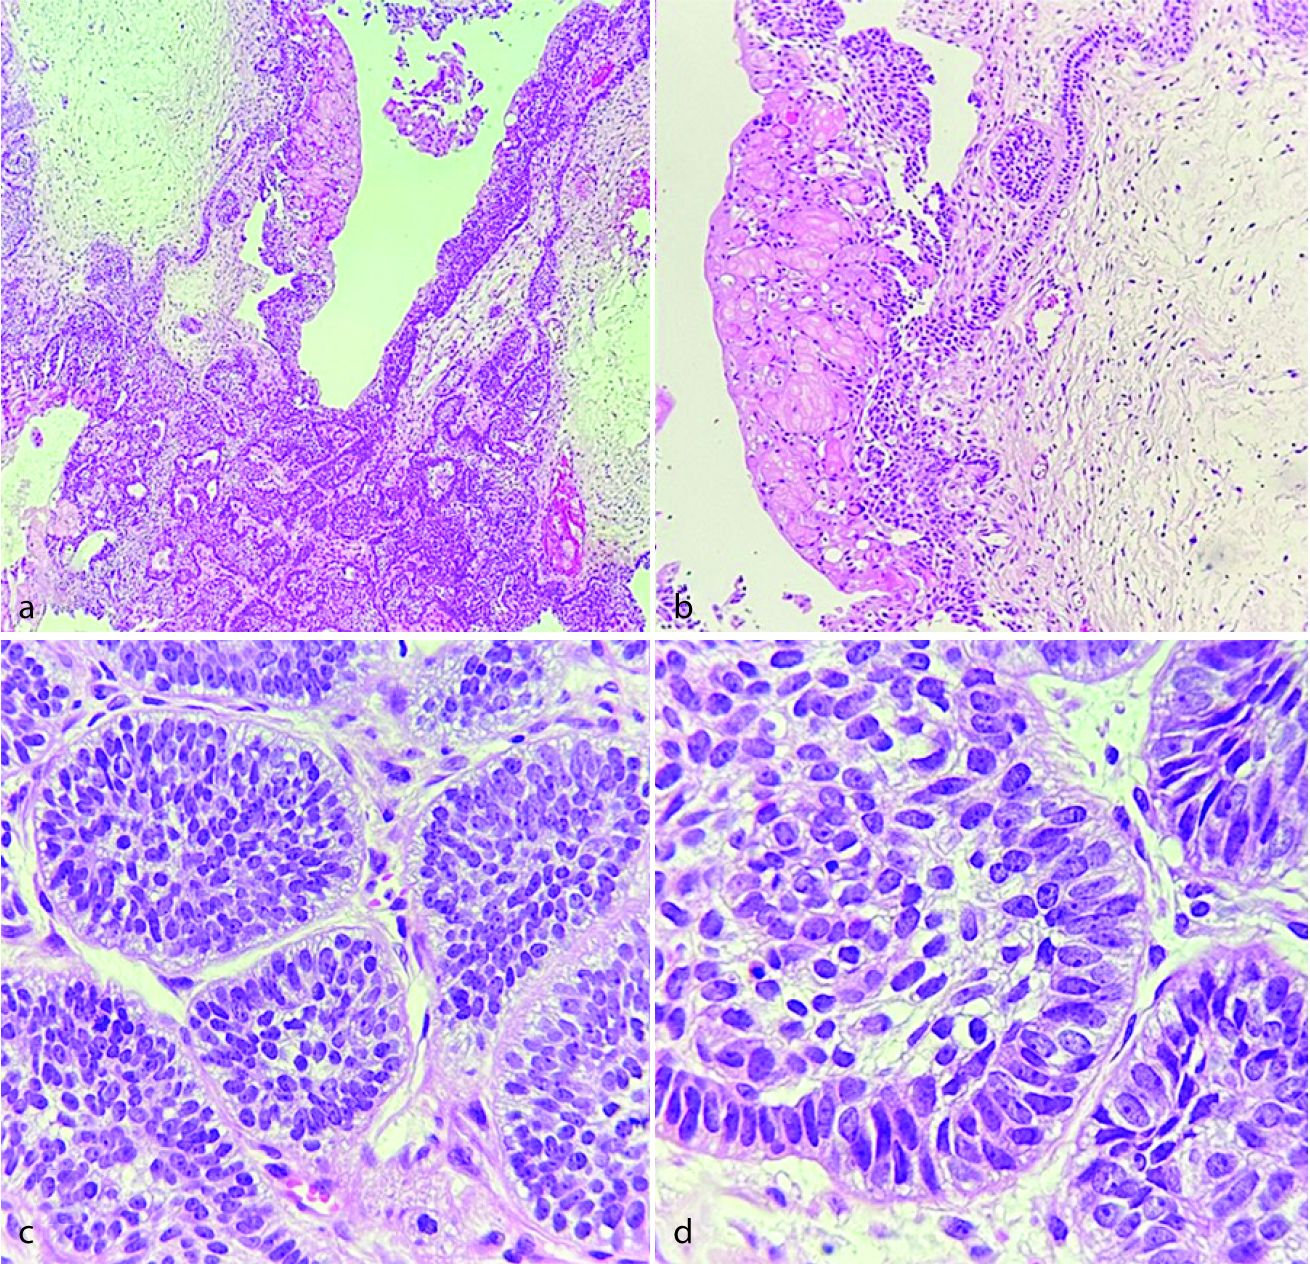

A glandular odontogenic cyst associated with ameloblastoma is an exceptionally rare microscopic feature with no known clinical significance or treatment applications. This lesion is mostly reported in men, mandible, affecting younger patients with an average age of 20.8. GOC may show microscopic characteristics that overlap with botryoid odontogenic cysts, DC, and low-grade mucoepidermoid carcinoma, but not with ameloblastoma [ 28 ]. In the histopathologic features of our case presented here, glandular features including squamous epithelium with surface cuboidal to columnar cells, hobnail appearance, focal nodular thickening, mucin-producing goblet cells, and duct-like spaces were evident. Interestingly, in some areas, a reverse polarity of the basal cells was also noted and the underlying connective tissue demonstrated scattered islands with ameloblastomatous changes (Figure 3).

Figure 3. Histopathologic sections of glandular odontogenic cyst/ameloblastoma, a: A cystic lesion lined by hyperplastic stratified squamous epithelium containing numerous mucous cells (Hematoxylin and eosin staining, 100×), b: The surface hobnail appearance (Hematoxylin and eosin staining, 400×), c: A duct-like space (Hematoxylin and eosin staining, 400×), d: The ameloblastic proliferation (Hematoxylin and eosin staining, 100×)